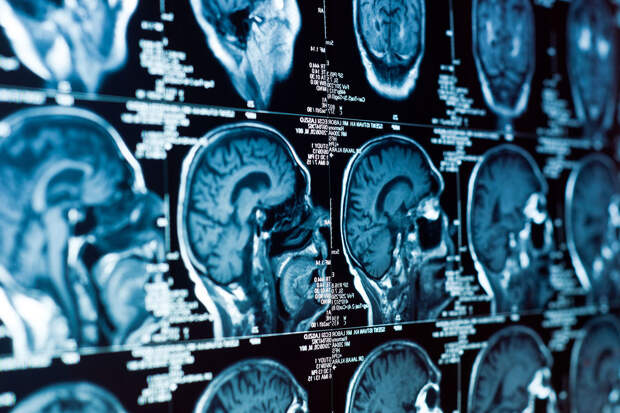

Исследователи из Пенсильванского университета обнаружили, что гидралазин — один из самых старых препаратов для снижения артериального давления — может замедлять рост опухолей мозга. Результаты работы опубликованы в журнале Science Advances (SciAdv).

Для глиобластомы — одной из самых агрессивных форм рака мозга — этот механизм особенно важен: опухолевые клетки часто существуют в условиях выраженной гипоксии и используют сигналы АДО, чтобы продолжать делиться.Когда гидралазин подавляет работу фермента, клетки теряют способность адаптироваться к дефициту кислорода. Они не погибают, как при химиотерапии, а переходят в состояние покоя или "старения", переставая активно размножаться. Это тормозит рост опухоли и при этом не вызывает дополнительного воспаления или устойчивости к лечению.

Чтобы подтвердить механизм, исследователи использовали рентгеновскую кристаллографию и визуализировали, как гидралазин связывается с ферментом. Затем препарат протестировали на клетках глиобластомы, и результаты подтвердили: блокирование АДО нарушает цикл адаптации к гипоксии.